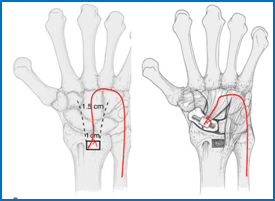

Surgery to treat a non union uses bone graft which may be taken from the hip or the radius.  The bone used in grafting has lots of bone healing cells in it, when placed in the fracture site it helps the non-union to heal.  When taken from the hip only a 1cm chunk of bone is removed, however the operation site is reported as being very painful for a few weeks.  The wound and dressings should be treated in the same way as the wrist wound (see below).   The non union site is cleaned back to healthy bleeding bone.  The bone graft is then packed into the gap and held with a headless screw.

This is the term given to bone which has died because it has not got a blood supply; typically affecting non union of a proximal pole fracture.   The bone may look white on an x-ray or show up as dark on an MRI scan.  Because the bone is dead it had 'turned to chalk' and is very difficult to get to heal.  In this instance a vascularised bone graft may be used.  This involves taking a piece of bone from the radius that unlike the bone graft used normally, has a small blood vessel feeding it.  Next the small square of bone with the vessel and placing it is lifted into the non union site.  In this way the blood supply is plumbed directly into the dead bone.  Even with this advanced surgery the success rate of gaining a healthy united scaphoid in the presence of AVN is only 40-55%.